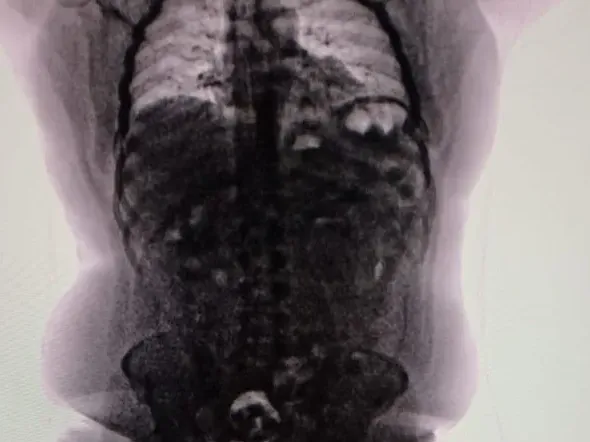

Tras un control con escáner corporal, se confirmó que transportaba múltiples cuerpos extraños en su interior. Fue inmediatamente internado en el Hospital de Ezeiza, donde permaneció bajo estricta vigilancia médica y policial durante cuatro días, período en el cual evacuó las 90 cápsulas que totalizaron 698 gramos de cocaína.